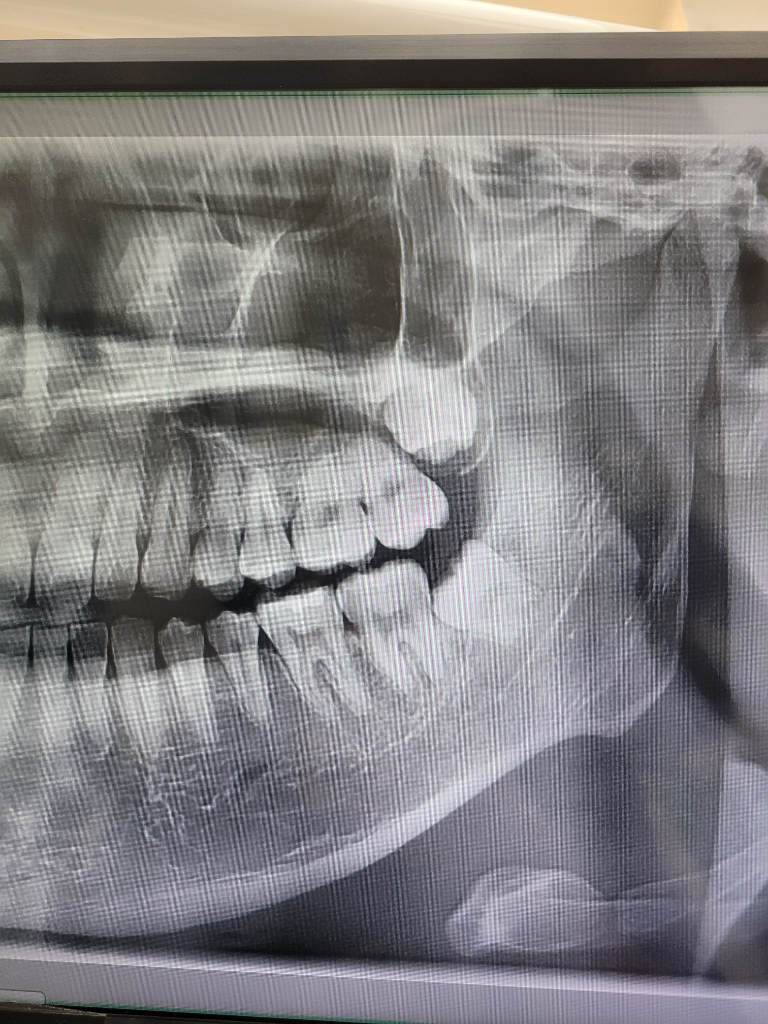

사랑이를 뽑게되면 앞의 지하에 주변에 치조골의 양이 줄어들기 때문에 인접치아가의 버티는 힘이 약해지게 됩니다.

이런 상태에서 앞에 치의 과도한 힘이 가해지면 통증이 심해질 수 있습니다. 이런 부분은 사랑니를 발치한 부분이 아물면서 대부분 괜찮아지기 때문에 그 이전까지 해당에 치아에 강한힘이 가해지지 않도록 해주는 것이 좋습니다.

원래 그렇다기 보다는 잇몸깊이 있어서 뼈를 삭제하는 등의 시술 방법에 따라 치아가 더 아프기도 합니다.

사랑니 발치후에 주변 치아도 충격 및 자극을 받아 통증이 유발될수 있습니다. 시간이 지남에 따라 대부분 좋아지게 되나 만약 통증이 지속되는 경우에는 치과진료를 받길 권합니다.

사랑니 발치를 한경우 통증이 심한경우도 잇습니다. 치아를 눌러서 뽑기 때문에 주변치아나 턱이 아플수도 잇습니다 .